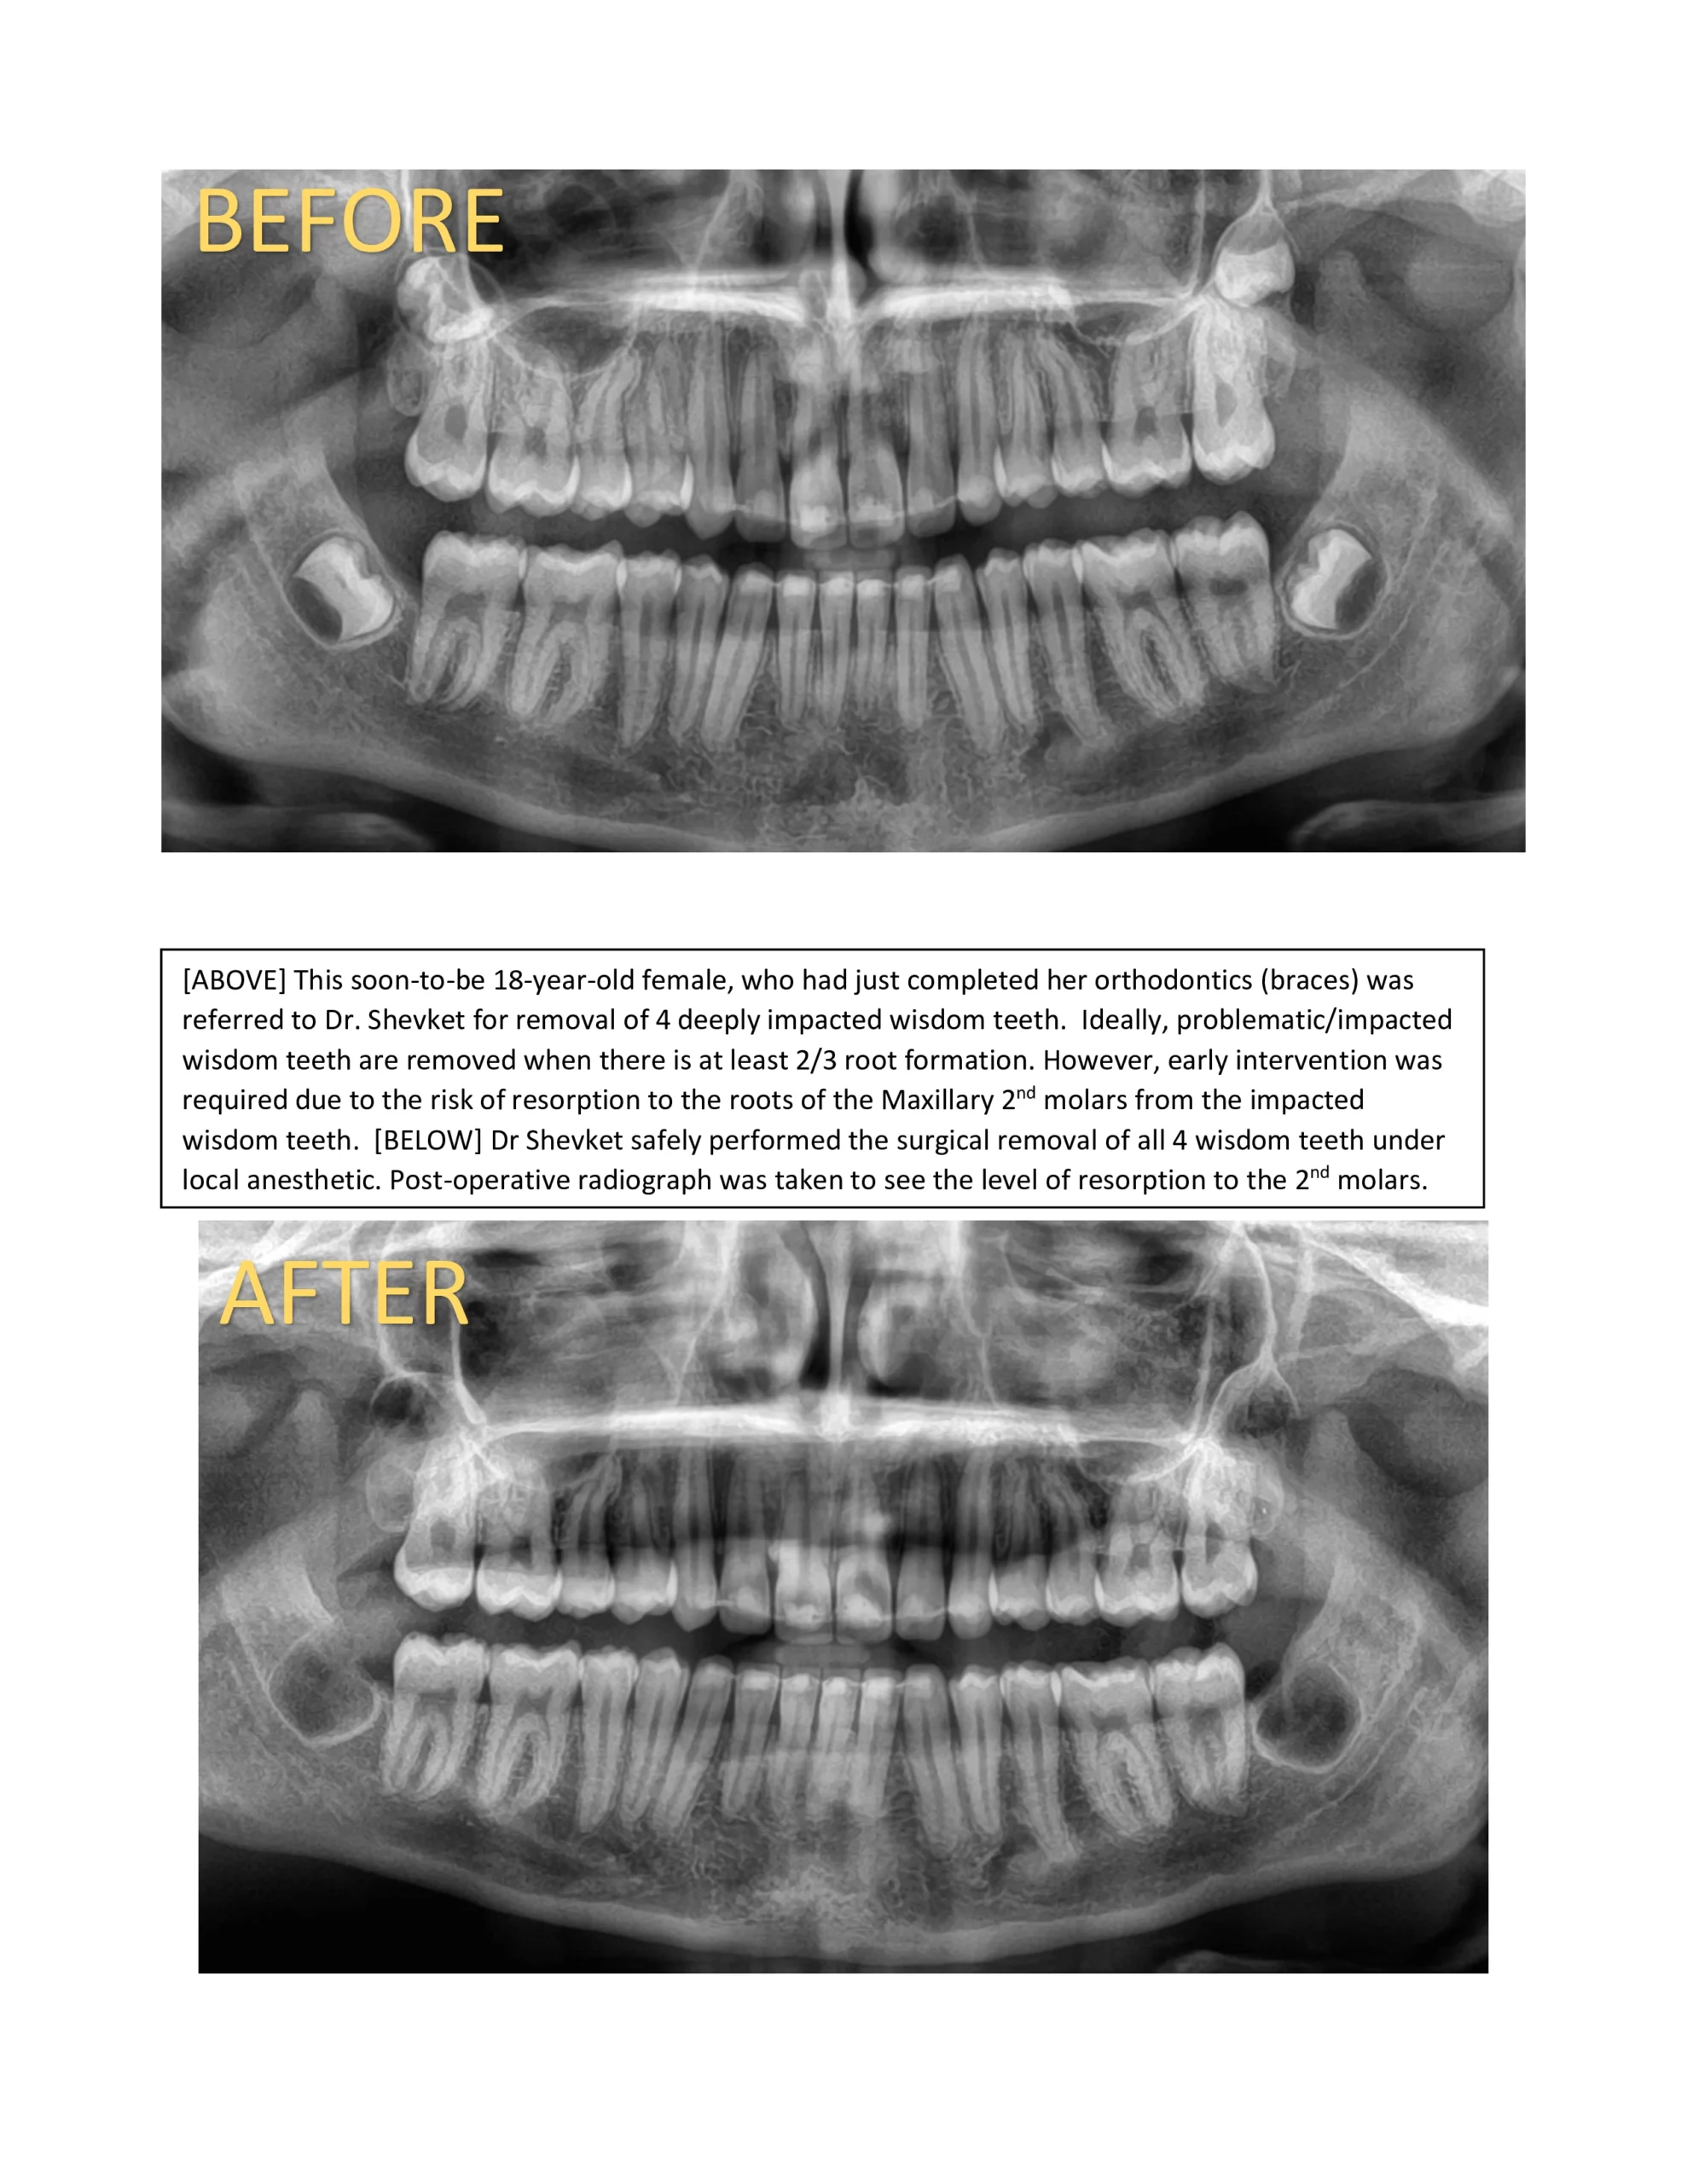

Let Dr. Shevket evaluate your case, and he will give you his professional opinion whether your wisdom teeth are impacted, and require extraction. BOOK a complimentary consultation now – TEXT OR EMAIL